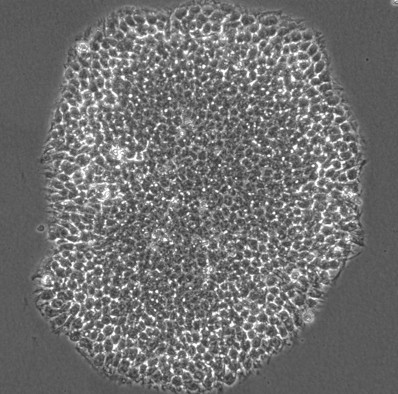

独自の高効率ゲノム編集技術を用いて作製したHLA(ヒト白血球抗原)の発現を抑制した高品質なヒトiPS細胞「StemEdit™ Human iPSC non-HLA」シリーズを、本日より研究用に提供開始いたします。本シリーズには、HLAクラスIおよびクラスIIの両方の発現を抑制した「B2M/CIITAダブルノックアウト株」と、HLAクラスIの発現を選択的に抑制した「B2Mシングルノックアウト株」の2種類が含まれます。